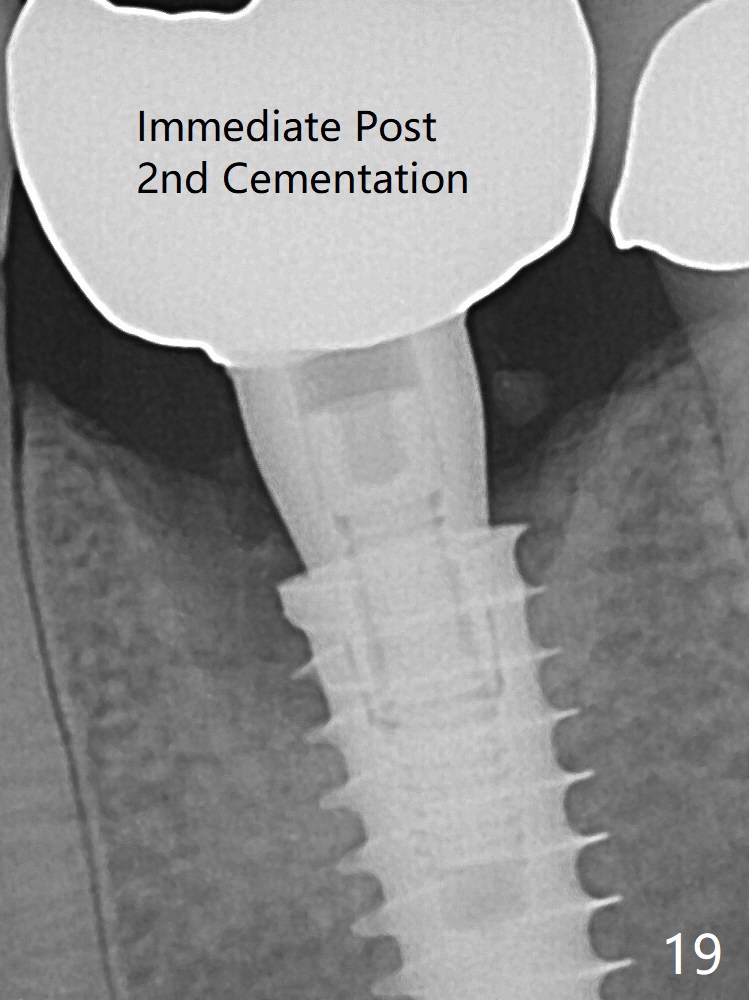

The gingiva looks healthy 8 months postop (3 months post cementation (after abutment screw retightening and addition of porcelain to proximal surfaces, Fig.12). New bone has apparently covered the implant plateau (Fig.13 arrows). Bone density between threads increases 9 months post cementation (Fig.14). There is 2 mm bone superior to the implant plateau mesial and distal 1 year 9 months post cementation (Fig.15,16). The crown/abutment is loose 3 times (3 months (Fig.14), 11 months (between Fig.14 and 15) and 2 years 3 months post cementation). In spite of being stable 3 years 10 months post cementation, a smaller abutment is placed (Fig.17 (PA), 18 (BW)) with impression for a new crown. After intraoral cementation, the new crown/abutment is removed for residual cement removal. When the complex is reseated, it is not smooth, probably due to proximal undercut. Fortunately the abutment appears to be completely seated, followed by 20 Ncm torque (Fig.19).